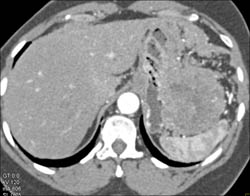

Antral Carcinoma